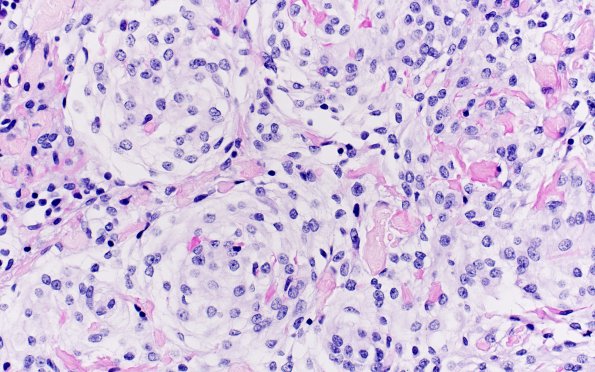

Washington University Experience | NEOPLASMS (MENINGIOMA) | Meningioma - Clear cell | 20D3 Clear cell meningioma (Case 20) PASW 40X 2

Diastase diminishes the PAS reactivity of individual tumor cells but not vascular wall staining (PAS-D)